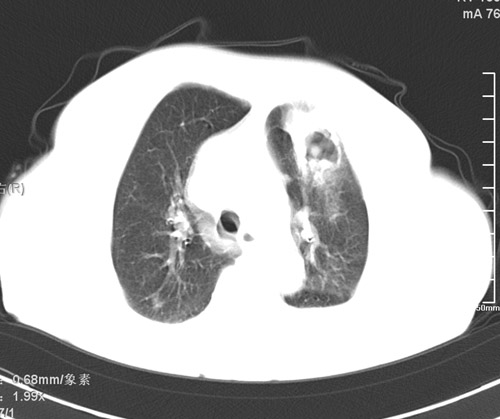

以下是引用杀毒软件在2009-4-22 18:45:00的发言:[br]考虑----左肺感染性病变〔真菌可能性大〕-----建议痰检。